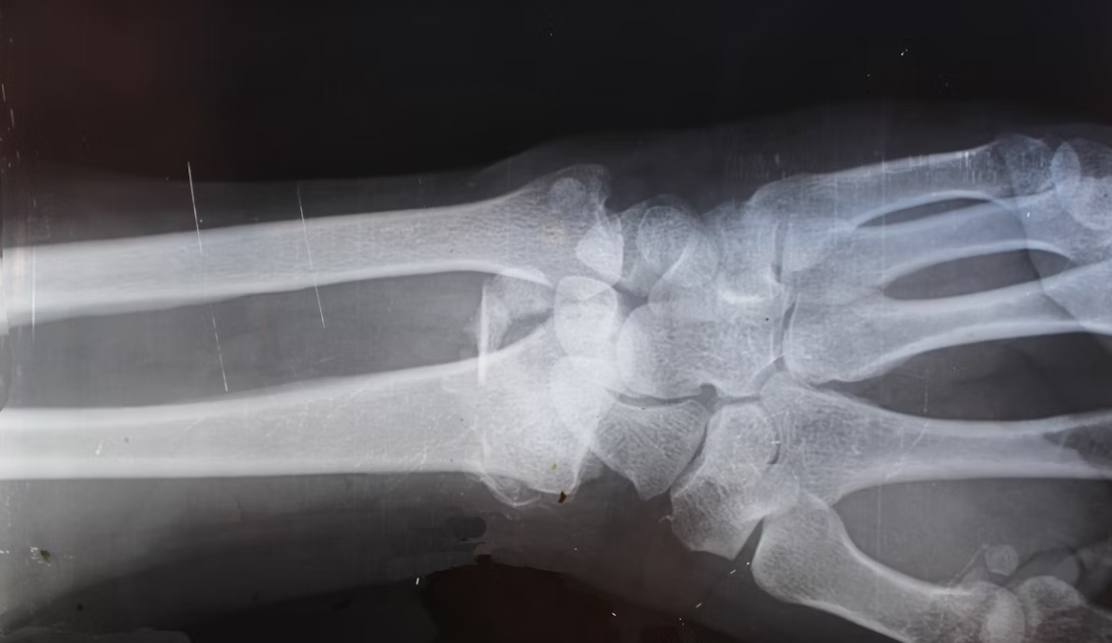

One of the primary benefits of orthopedic healthcare investing lies in the stability and continuous growth of the market. With aging populations and increasing cases of joint disorders, fractures, and chronic bone diseases, the demand for orthopedic care continues to expand. Younger generations also contribute to this demand through sports and fitness activities that lead to injury treatments and rehabilitation needs.